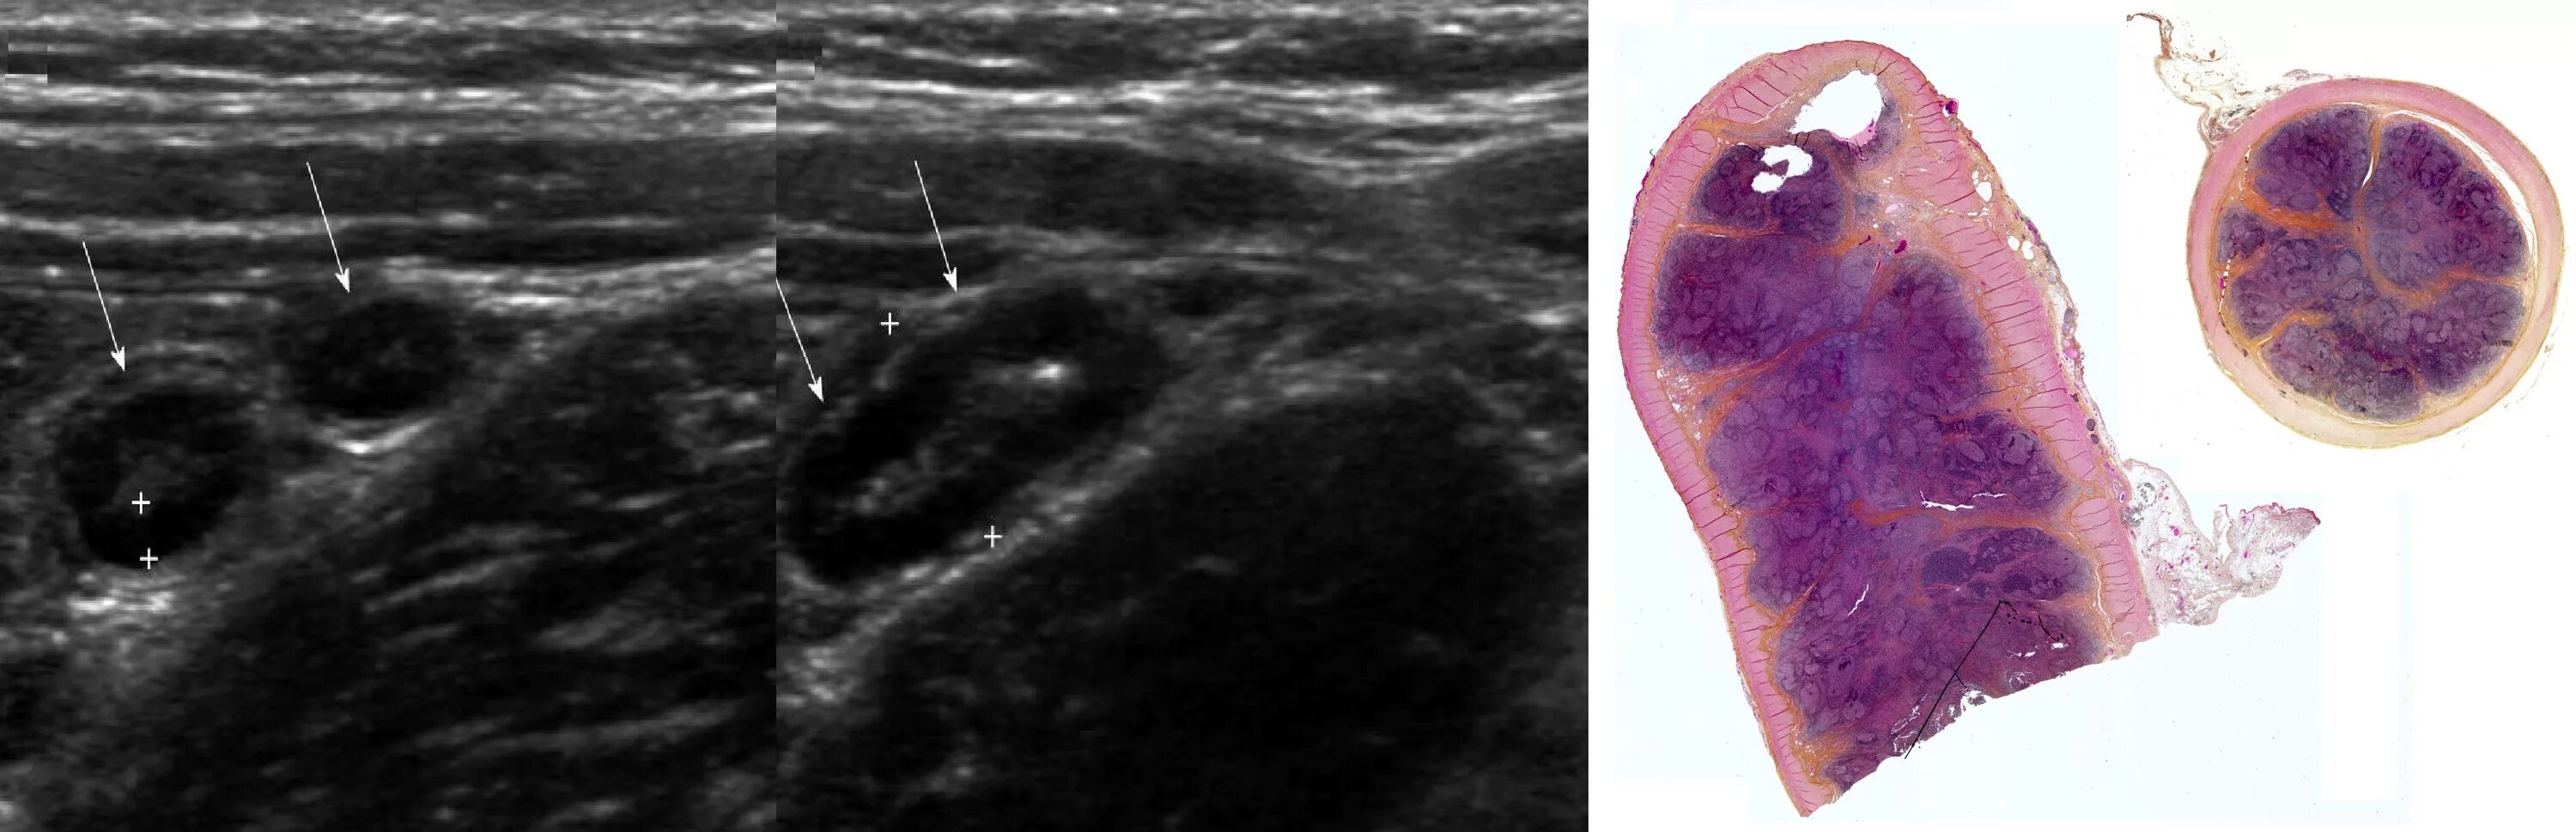

Аппендицит на узи можно ли